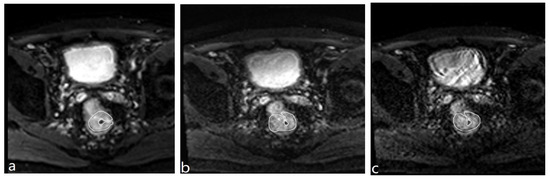

3.3. Quantitative Image Quality Analysis